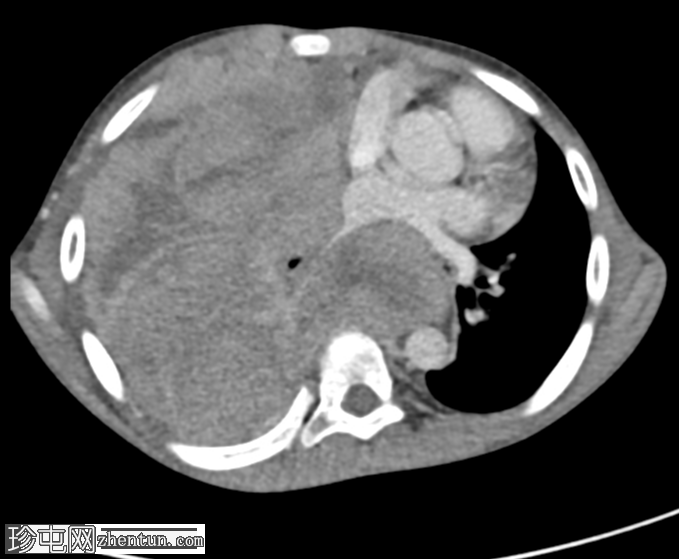

CT 发现:

一个大的、不均匀强化的肿块占据整个右半胸腔,导致右肺几乎完全塌陷。肿块延伸至纵隔,导致观察到的纵隔移位。病灶内未见钙化。此外,右侧第三和第八肋骨后方可见轻微骨膜反应。

右侧第三和第八肋骨后方可见轻微骨膜反应,为反应性反应,不提示骨源性。肿瘤环绕右肺叶,提示其来源于胸膜。骨外尤文氏肉瘤也可起源于胸壁、肺或纵隔。它是一种恶性肿瘤,通常影响儿童和青少年。